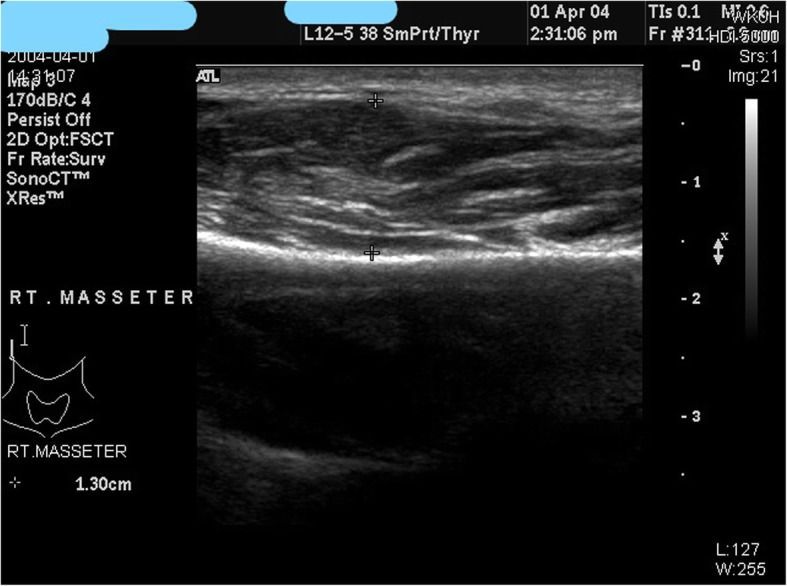

Khi hiệu quả của botulinum toxin được đánh giá dựa trên lực nhai và mức độ co thắt của cơ nhai, mức giảm trung bình 20% trong 6 tháng được duy trì và sự co thắt của cơ nhai được duy trì ở mức khoảng 30% trong 6 tháng (Hình 8). Chúng tôi sẽ chuẩn bị một tiêu chuẩn để kiểm tra và đánh giá sự co thắt của cơ nhai thông qua hình ảnh siêu âm để có thể dễ dàng thực hiện trong phòng khám. Chúng tôi hiện đang làm nghiên cứu về việc sử dụng các hình ảnh siêu âm để xác định mức độ phì đại cơ cắn và độ dày của cơ cắn ở nam giới và phụ nữ trưởng thành (Hình 9).

Sau nghiên cứu này, chúng tôi hy vọng rằng có thể thiết lập được một tiêu chuẩn cho vấn đề hàm bạnh, tìm ra liều lượng, phương pháp đánh giá và thời gian tiến hành lần tiêm thứ hai.